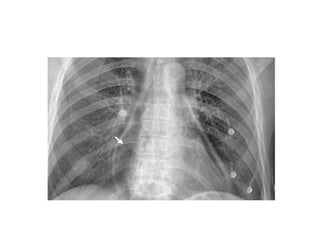

CXR findings ?

Chest radiography (Panel A) revealed cardiomegaly (cardiothoracic ratio, 0.86), splaying of the carina, and an elevated left main bronchus (arrows). Plus PPM DDD

Echocardiogram showed massive biatrial enlargement (left larger than right),

An 83-year-old woman with long-standing atrial fibrillation who had previously undergone atrioventricular nodal ablation and pacemaker placement presented with symptoms of progressive heart failure. The patient was discharged home on medical management after prolonged diuresis.